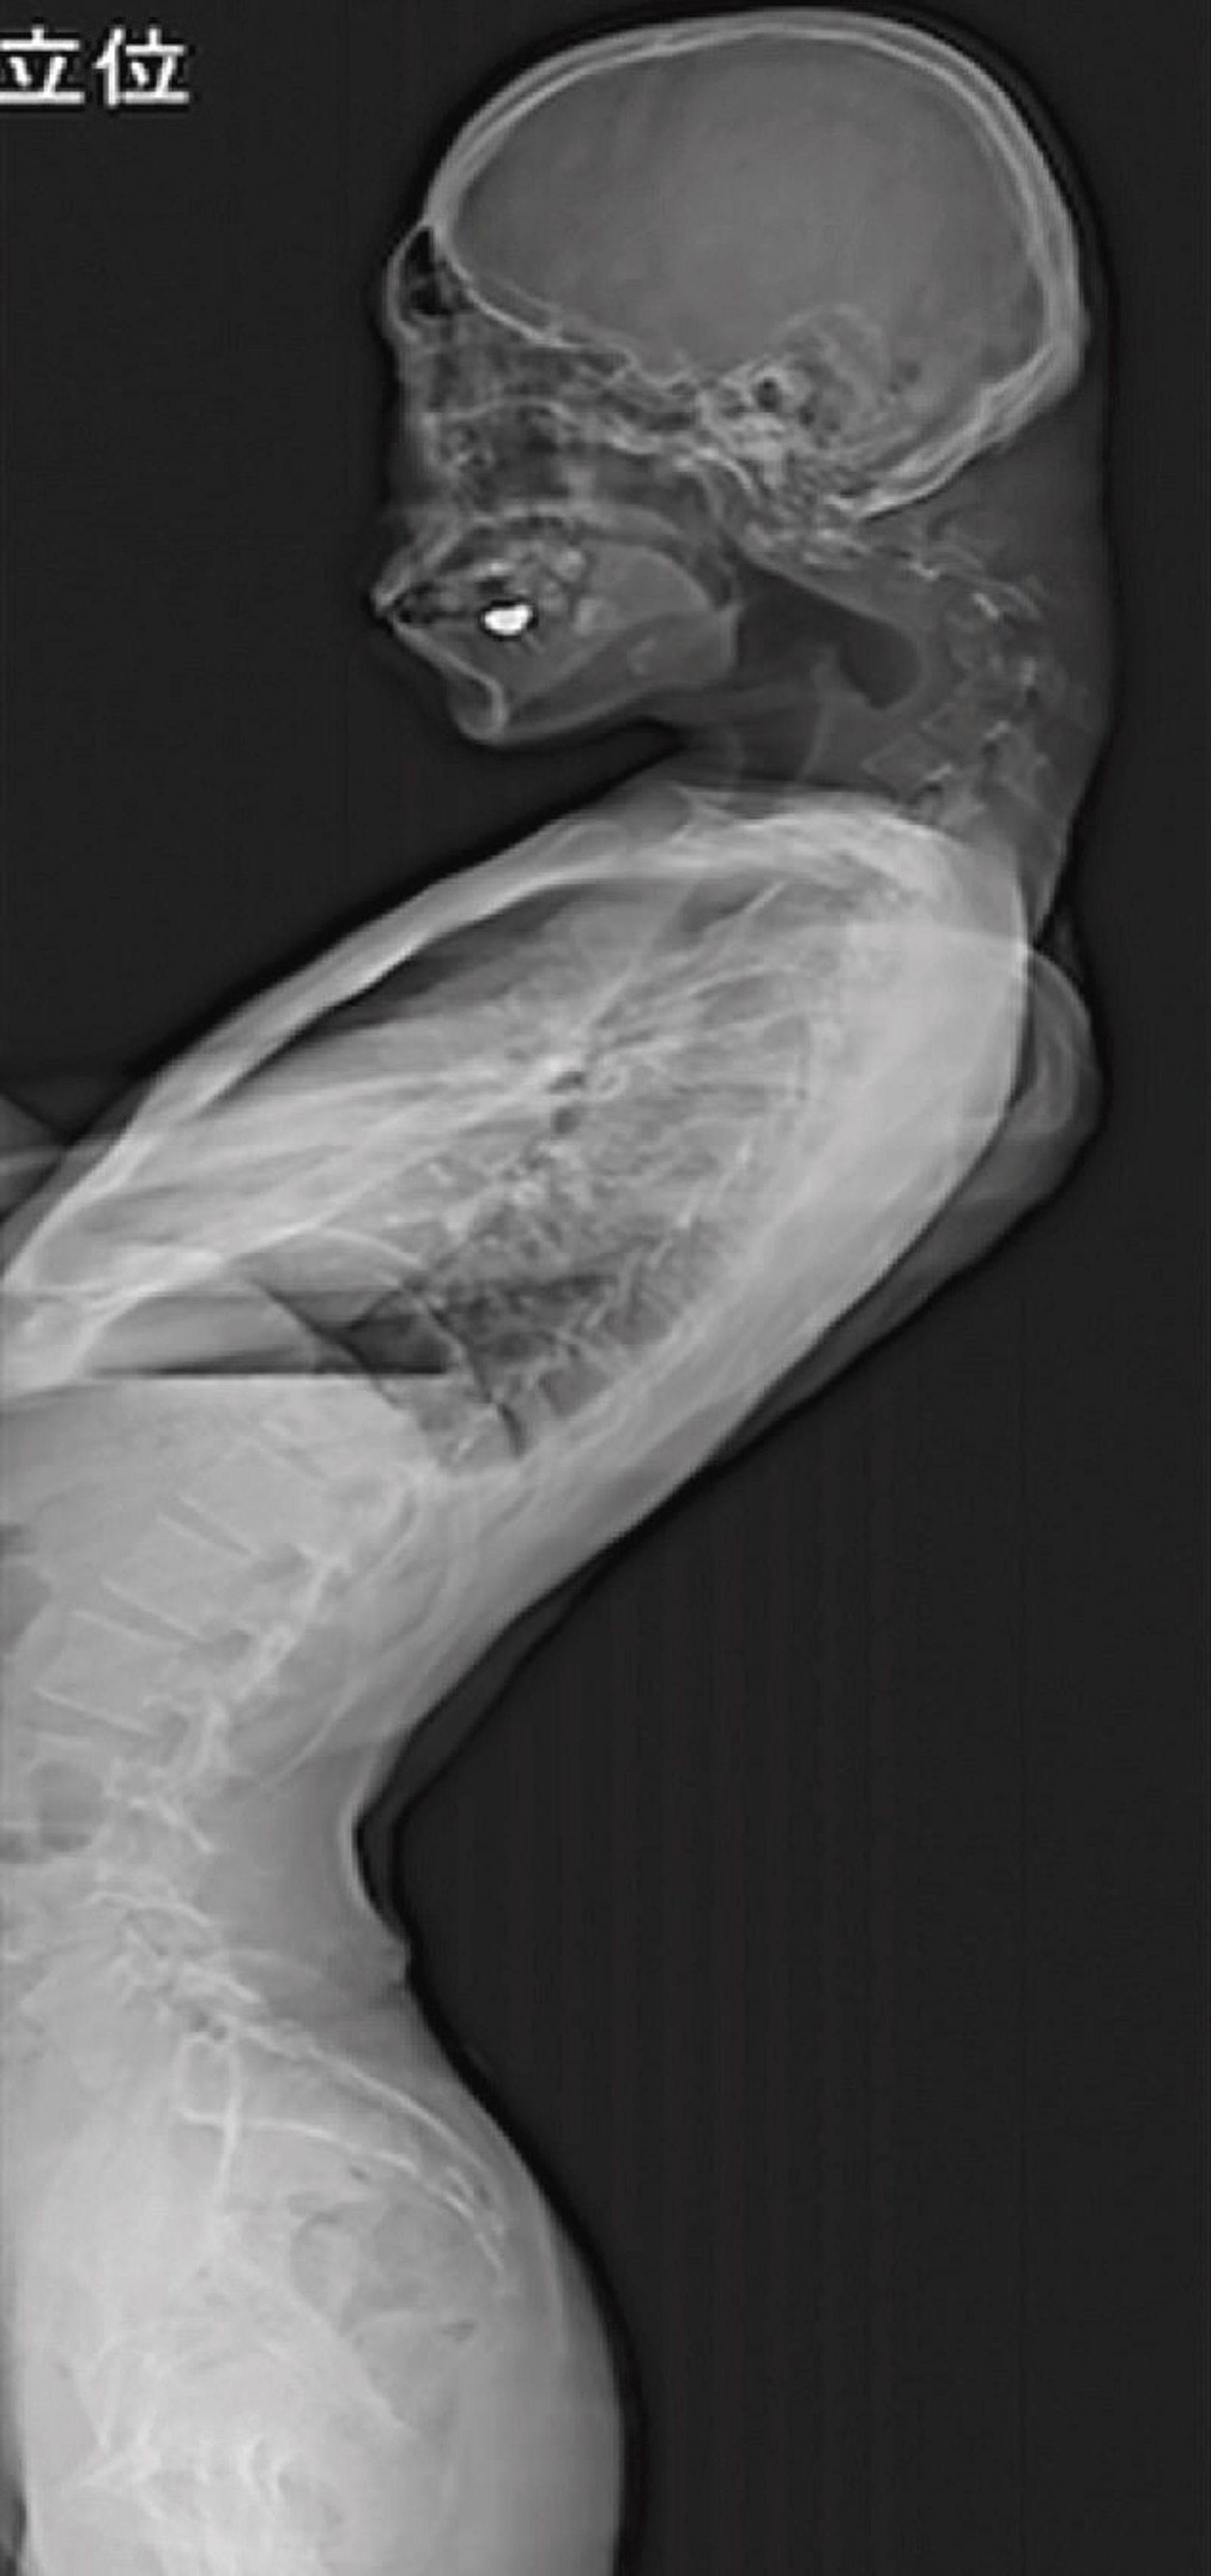

男子後來發現,自己出現難以吞嚥進食、頸部疼痛,而且有長達半年的時間,頸椎疼痛的程度變得更加激烈,而且男子完全「抬不起頭」,也導致他無法正常進食而體重下降。男子之後就醫,醫師發現男子的頸椎以經完全變形,後頸椎還突出一塊。

醫師原本嘗試用物理治療方式,讓男子以護頸支撐矯正,但效果不佳,男子也出現麻木不適的狀況,因此醫師決定採用手術方式。醫師切除變形的部分頸椎骨,之後在以「鎖螺絲」的方式,讓頸椎骨固定。男子在術後6個月恢復狀況良好,也能正常抬頭,進食吞嚥的功能也逐漸恢復,而且追蹤1年後也未復發。